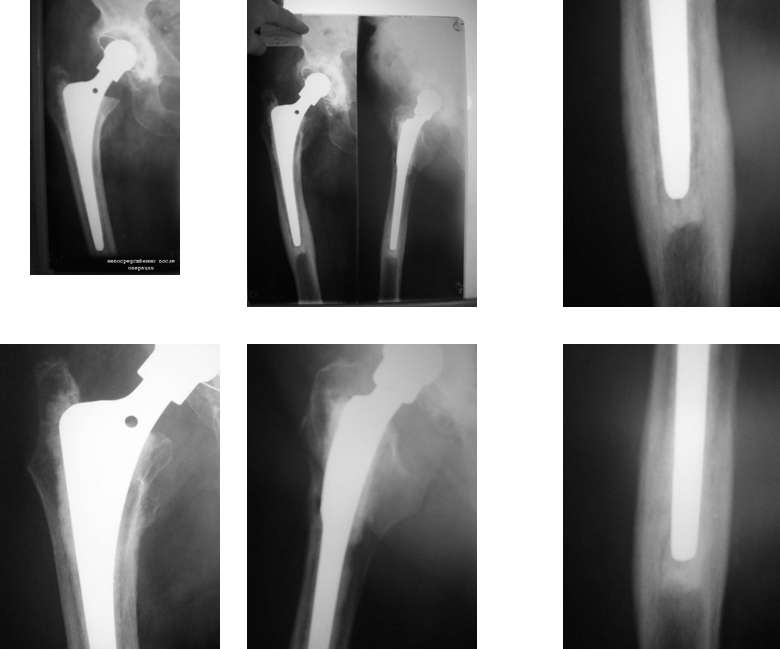

Уважаемые коллеги, у больной после цементного эндопротезирования т/бедренного сустава в течении 1.5 лет сохраняются боли при нагрузке от крыла подвздошной кости до с\3 бедра.

На Ro обнаружен периостит у верхушки ножки эндопротеза. Лейкоциты - 5,6; соэ - 11; С-реакт белок - 22.

Очень важна клиника. Как болит? когда? как с нагрузкой соотносится? Если в момент нагружения и потом в момент снятия нагрузки, то тут следует подозревать нестабильность ножки. В боковой проекции просветление вдоль мантии, утолщение кортикалов в дистальной части. Похоже, что ножка на постаменте. Был подобный случай, только рентгенологически не было никаких признаков. На ревизии совершенно нестабильная ножка.

Добрый вечер.Считаю,что на представленных R-граммах имеют место быть два

основных симптомокомплекса-

1.Проксимальный стресс-шилдинг

2.Дистальный стресс-байпасс.

Указанные синдромы подробно развернуты и объяснены (в т.ч. ответ на вопрос "Что делать?") с подобными непростыми последствиями-осложнениями

эндопротезирования в книге Р.М.Тихилова в соавт.2008